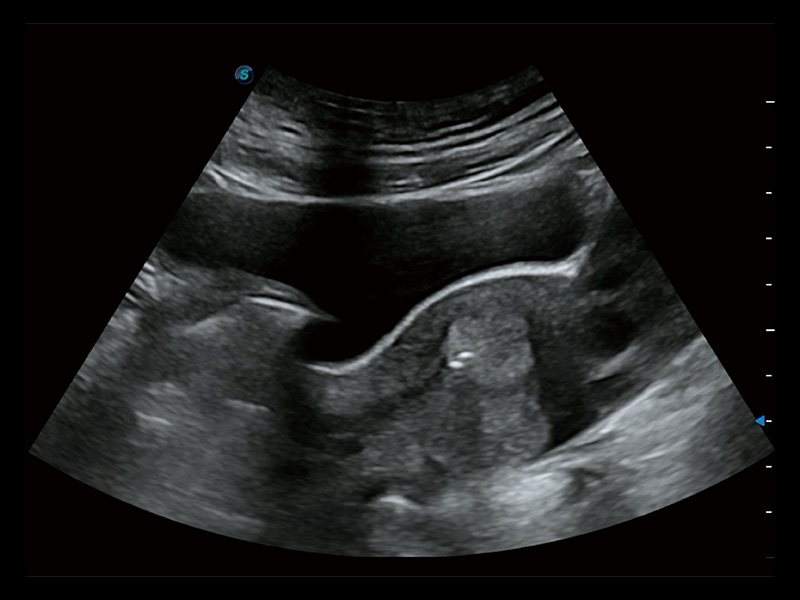

“生育问题”即关系民族复兴,也关系亿万家庭的幸福。随着婚育年龄推迟、社会压力增加等因素,越来越多人群也面临着“生不出、生不好”的问题。辅助生殖作为治疗不孕不育最有效的方法之一,也逐渐成为育儿新希望。而超声检查能为生殖需求人群的初诊评估提供宝贵的信息。 P20 Elite是狗万官方网站匠心打造的一款生殖应用型彩超。她继承狗万官方网站高端极光平台,突破性地将多款新型芯片及硬件模块进行整合,均衡了高端系统性能与小巧灵动机身。P20 Elite卓越的图像质量搭载专科探头,旨在为您提供全面的辅助生殖解决方案。

P20 Elite配备了丰富的生殖探头群和临床应用功能,在卵泡监测、穿刺取卵、胚胎移植、妊娠确认等领域,为生殖需求人群提供了新的临床机会,重新定义高端超声如何应用于生殖健康检查。